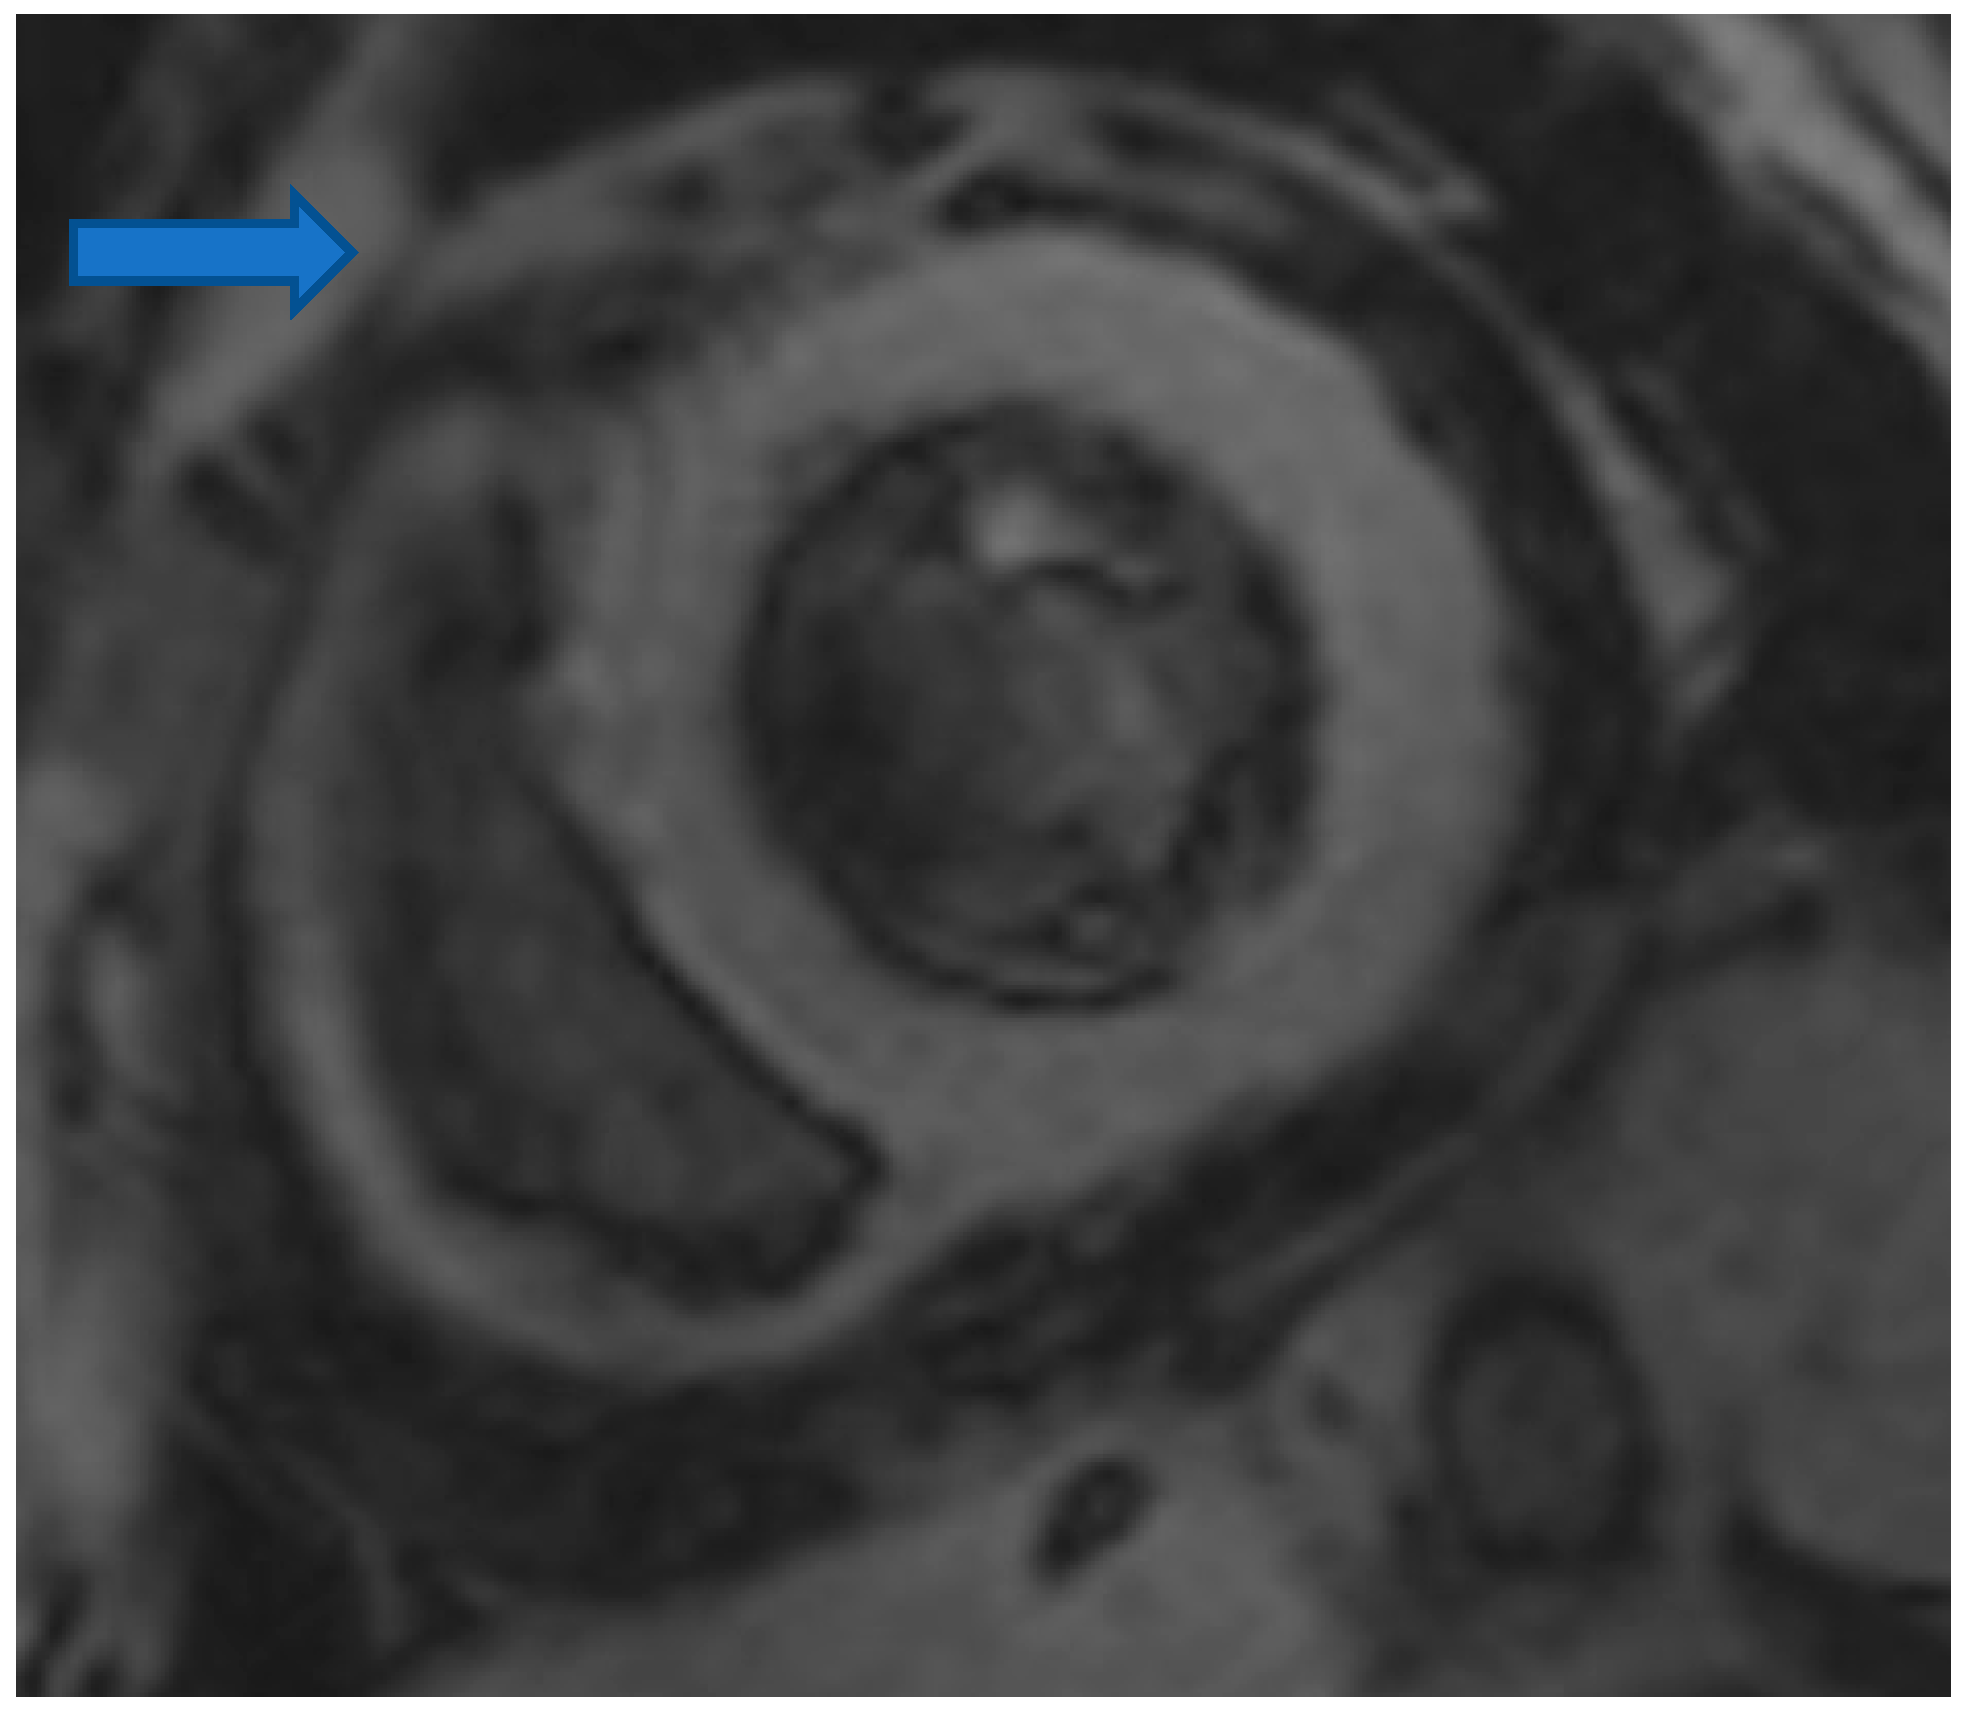

4.5. Myocardial Edema-Fibrosis Assessment

- Mavrogeni, S.; Pepe, A.; Nijveldt, R.; Ntusi, N.; Sierra-Galan, L.M.; Bratis, K.; Wei, J.; Mukherjee, M.; Markousis-Mavrogenis, G.; Gargani, L.; et al. Cardiovascular magnetic resonance in autoimmune rheumatic diseases: A clinical consensus document by the European Association of Cardiovascular Imaging. Eur. Heart J. Cardiovasc. Imaging 2022, 23, e308–e322. [Google Scholar] [CrossRef]